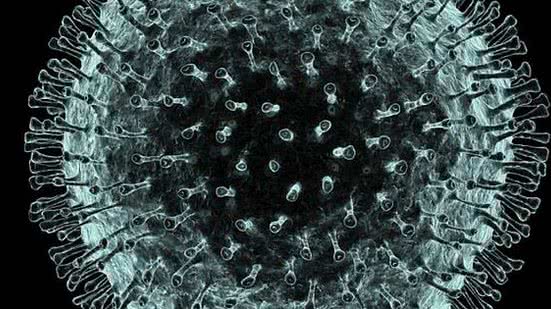

O estado do Rio de Janeiro vai realizar um workshop na segunda-feira (17) para atualizar e padronizar os protocolos de controle do coronavírus. O secretário de Estado de Saúde, Edmar Santos, afirmou que não há circulação do coronavírus em território fluminense, mas que a reunião é importante para que os municípios se antecipem e estejam preparados para o enfrentamento adequado.

"Nós estamos nos preparando com tudo o que é necessário em termos de planejamento. Caso o coronavírus chegue aqui, poderemos fazer o enfrentamento adequado e não ter a população sob risco desnecessário", explicou Santos.

Segundo ele, estarão presentes no evento todos os secretários de Saúde e subsecretários de Vigilância em Saúde municipais do estado, representações dos hospitais militares, universitários e privados.

"A gente vai fazer a apresentação do plano de contingência, oficinas para deixar muito claro o fluxo de acompanhamento para diagnóstico, isolamento domiciliar, para internação, quem interna e quem não interna. Isso será amplamente debatido com todos aqueles que fazem a saúde do estado Rio de Janeiro, para que não haja nenhuma dúvida sobre o plano de contingência, que está absolutamente alinhado com o do Ministério da Saúde."

O secretário antecipou as informações sobre o workshop durante coletiva de imprensa para confirmar o primeiro caso de morte por sarampo no estado em 20 anos.